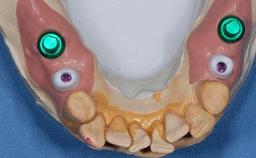

The patient presented with a failing tooth-supported fixed dental prosthesis with cantilever extension replacing the right maxillary central incisor. His chief presenting complaint was poor esthetics, in particular the dark discolored margin around the abutment tooth, the maxillary left central incisor. He reported a history of trauma at a young age, which necessitated the replacement of his maxillary right central incisor as well as root canal therapy of the adjacent left central incisor. The existing prosthesis had been in situ for over 20 years. The initial periapical radiograph displayed good proximal bone levels at the adjacent teeth and a wide incisive canal, which was a concern. The left central incisor presented a very wide root canal treatment with compromised radicular dentin thickness, which was a consideration in the decision between a new tooth-supported fixed dental prosthesis vs. an implant-supported prosthesis. After a lengthy discussion on the risks and benefits of both treatment options, the patient decided on a single-tooth implant replacement.

Prosthesis Type FDP

Retention Cemented, with meso-structure Cemented, with meso-structure